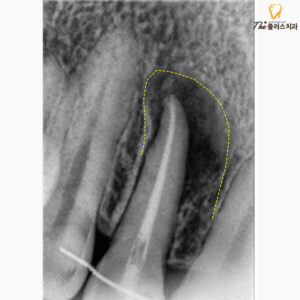

바로 상태를 면밀히 살펴보기 위해

엑스레이 촬영을 진행하였고,

촬영 결과 신경치료한 부위의

치아 뿌리 끝 염증이 크게 자리 잡고 있었습니다.